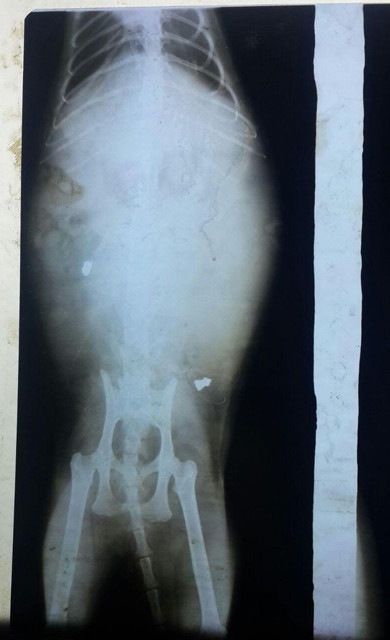

İZMİR Çeşmeli hayvanseverlerden Aytül Kayserili'nin evinde doğup büyüyen 'Lea' adlı kedi, evde kimse yokken, havalı tüfekle vuruldu. Aytül Kayserili'nin komşusu tarafından hemen veterinere götürülen Lea'nin çekilen röntgeninde, omiriliği delip geçerek yumuşak dokuya saplanan iki saçma tespit edildi. Olayı öğrenince büyük üzüntü yaşayan Kayserili, sosyal medyadaki, Çeşme- Alaçatı Sokak Hayvanları ve Barınağı Yardımlaşma Platformu'nda bir paylaşım yaparak şu sözlere yer verdi:

Önce köpek ısırığı sanıldı. Ama çekilen röntgende, omurgayı kırarak giren, yumuşak dokuda olan iki adet saçmayı gördük. Söylenecek çok şey var, ama maalesef yapacak hiçbir şey yok. Tek umudum tedavinin işe yaraması. Onlar, en az evlat gibi seviliyor, önemseniyor. Onlar beni hayata bağlıyor. Sevgimi en çok onlar hak ediyor."